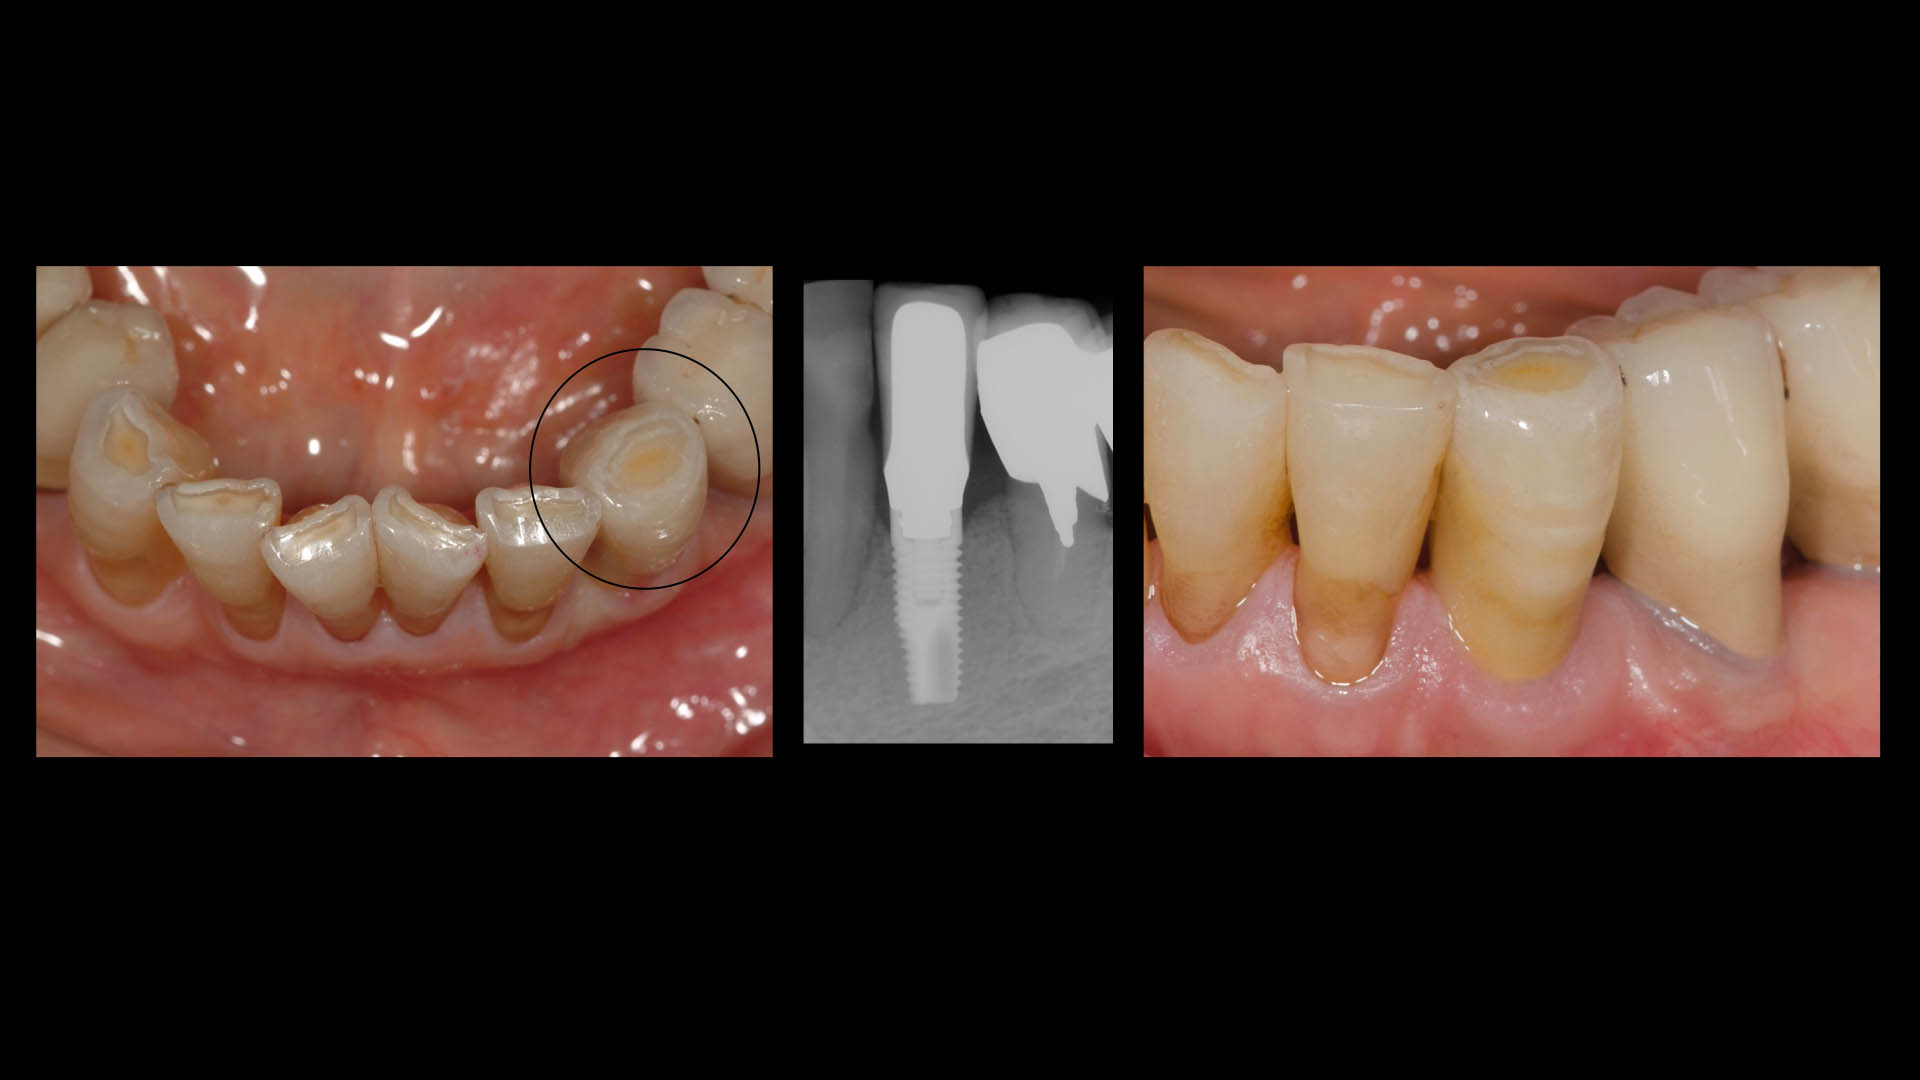

Take a glimpse into the magic of Coral Gables Dentistry through our before and after pictures. See firsthand the incredible smile makeover transformations that have brought confidence and joy to our patients.